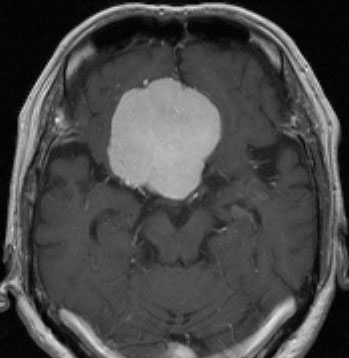

上矢状洞髄膜腫 superior sagittal sinus meningioma

上矢状洞を埋め尽くすように増大して,頭蓋骨浸潤が著しい髄膜腫ですが,ごく軽度の右足脱力以外に何の症状もありません。上矢状洞はゆっくり閉塞すれば,このような頭頂部から後頭部にわたる広範閉塞でも,静脈還流に障害がない場合が多いといえます。大脳の前半部の血流は前頭葉表面の皮質静脈から海綿静脈洞に側副路を形成しています。頭蓋内圧亢進所見もなく,これらはこの髄膜腫がゆっくり増大したということを示唆しています。

手術直後の画像です。全部いっぺんに摘出するのは無理なので,まず前から80%くらいの腫瘍を摘出しました。肥厚した骨はチタンプレートで置き換えてあります。後頭部の上矢状洞内と大脳鎌に少し残りましたが,この6ヶ月後に2回目の開頭術をして全摘出しました。結果的にこの例では,上矢状洞を冠状縫合のあたりから,静脈洞交会まで壁ごと全部摘出しましたが,脳浮腫も何も生じませんでした。腫瘍の両側にある皮質静脈 cortical veinsを損傷しないことが肝要です。

右の病理像は,頭蓋骨浸潤している部分 ですが,骨破壊は良性髄膜腫に特徴的な骨内浸潤像です。この骨浸潤像は悪性像とはいえません。MIB-1は高いところで8%、低いところで3%程度です。